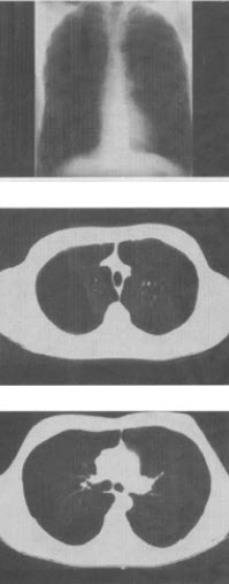

- 单项选择题 患者男,55岁,胸闷气急1周,无发热,结合图像,最可能的诊断是()。

- B